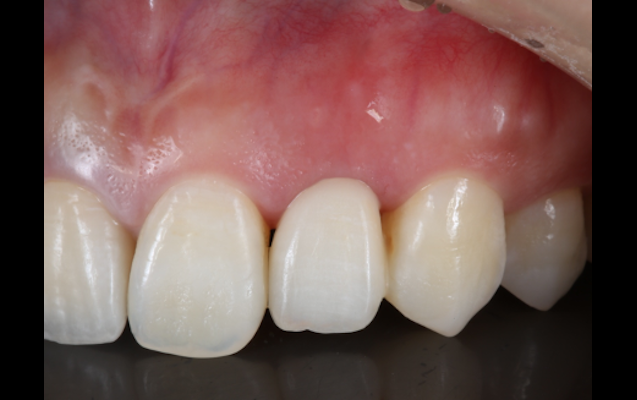

| 治療名 | 前歯接着性ブリッジ |

| 基礎データ | 46歳/女性 |

| 治療期間 | 4ヶ月 |

| 執刀医 | Dr. 大杉 |

| 治療費 |

30万円 ■内訳 接着性ブリッジ20万 抜歯窩温存術10万 |

| 概要 |

インプラント治療を希望されて来院された方ですが、治療期間・外科的侵襲を考慮し、セラミックでの治療を希望されました。側切歯(前から2番目の歯)の場合はこのような治療も可能です。 |

| 主な副作用 |

セラミック脱離、セラミック破損 |